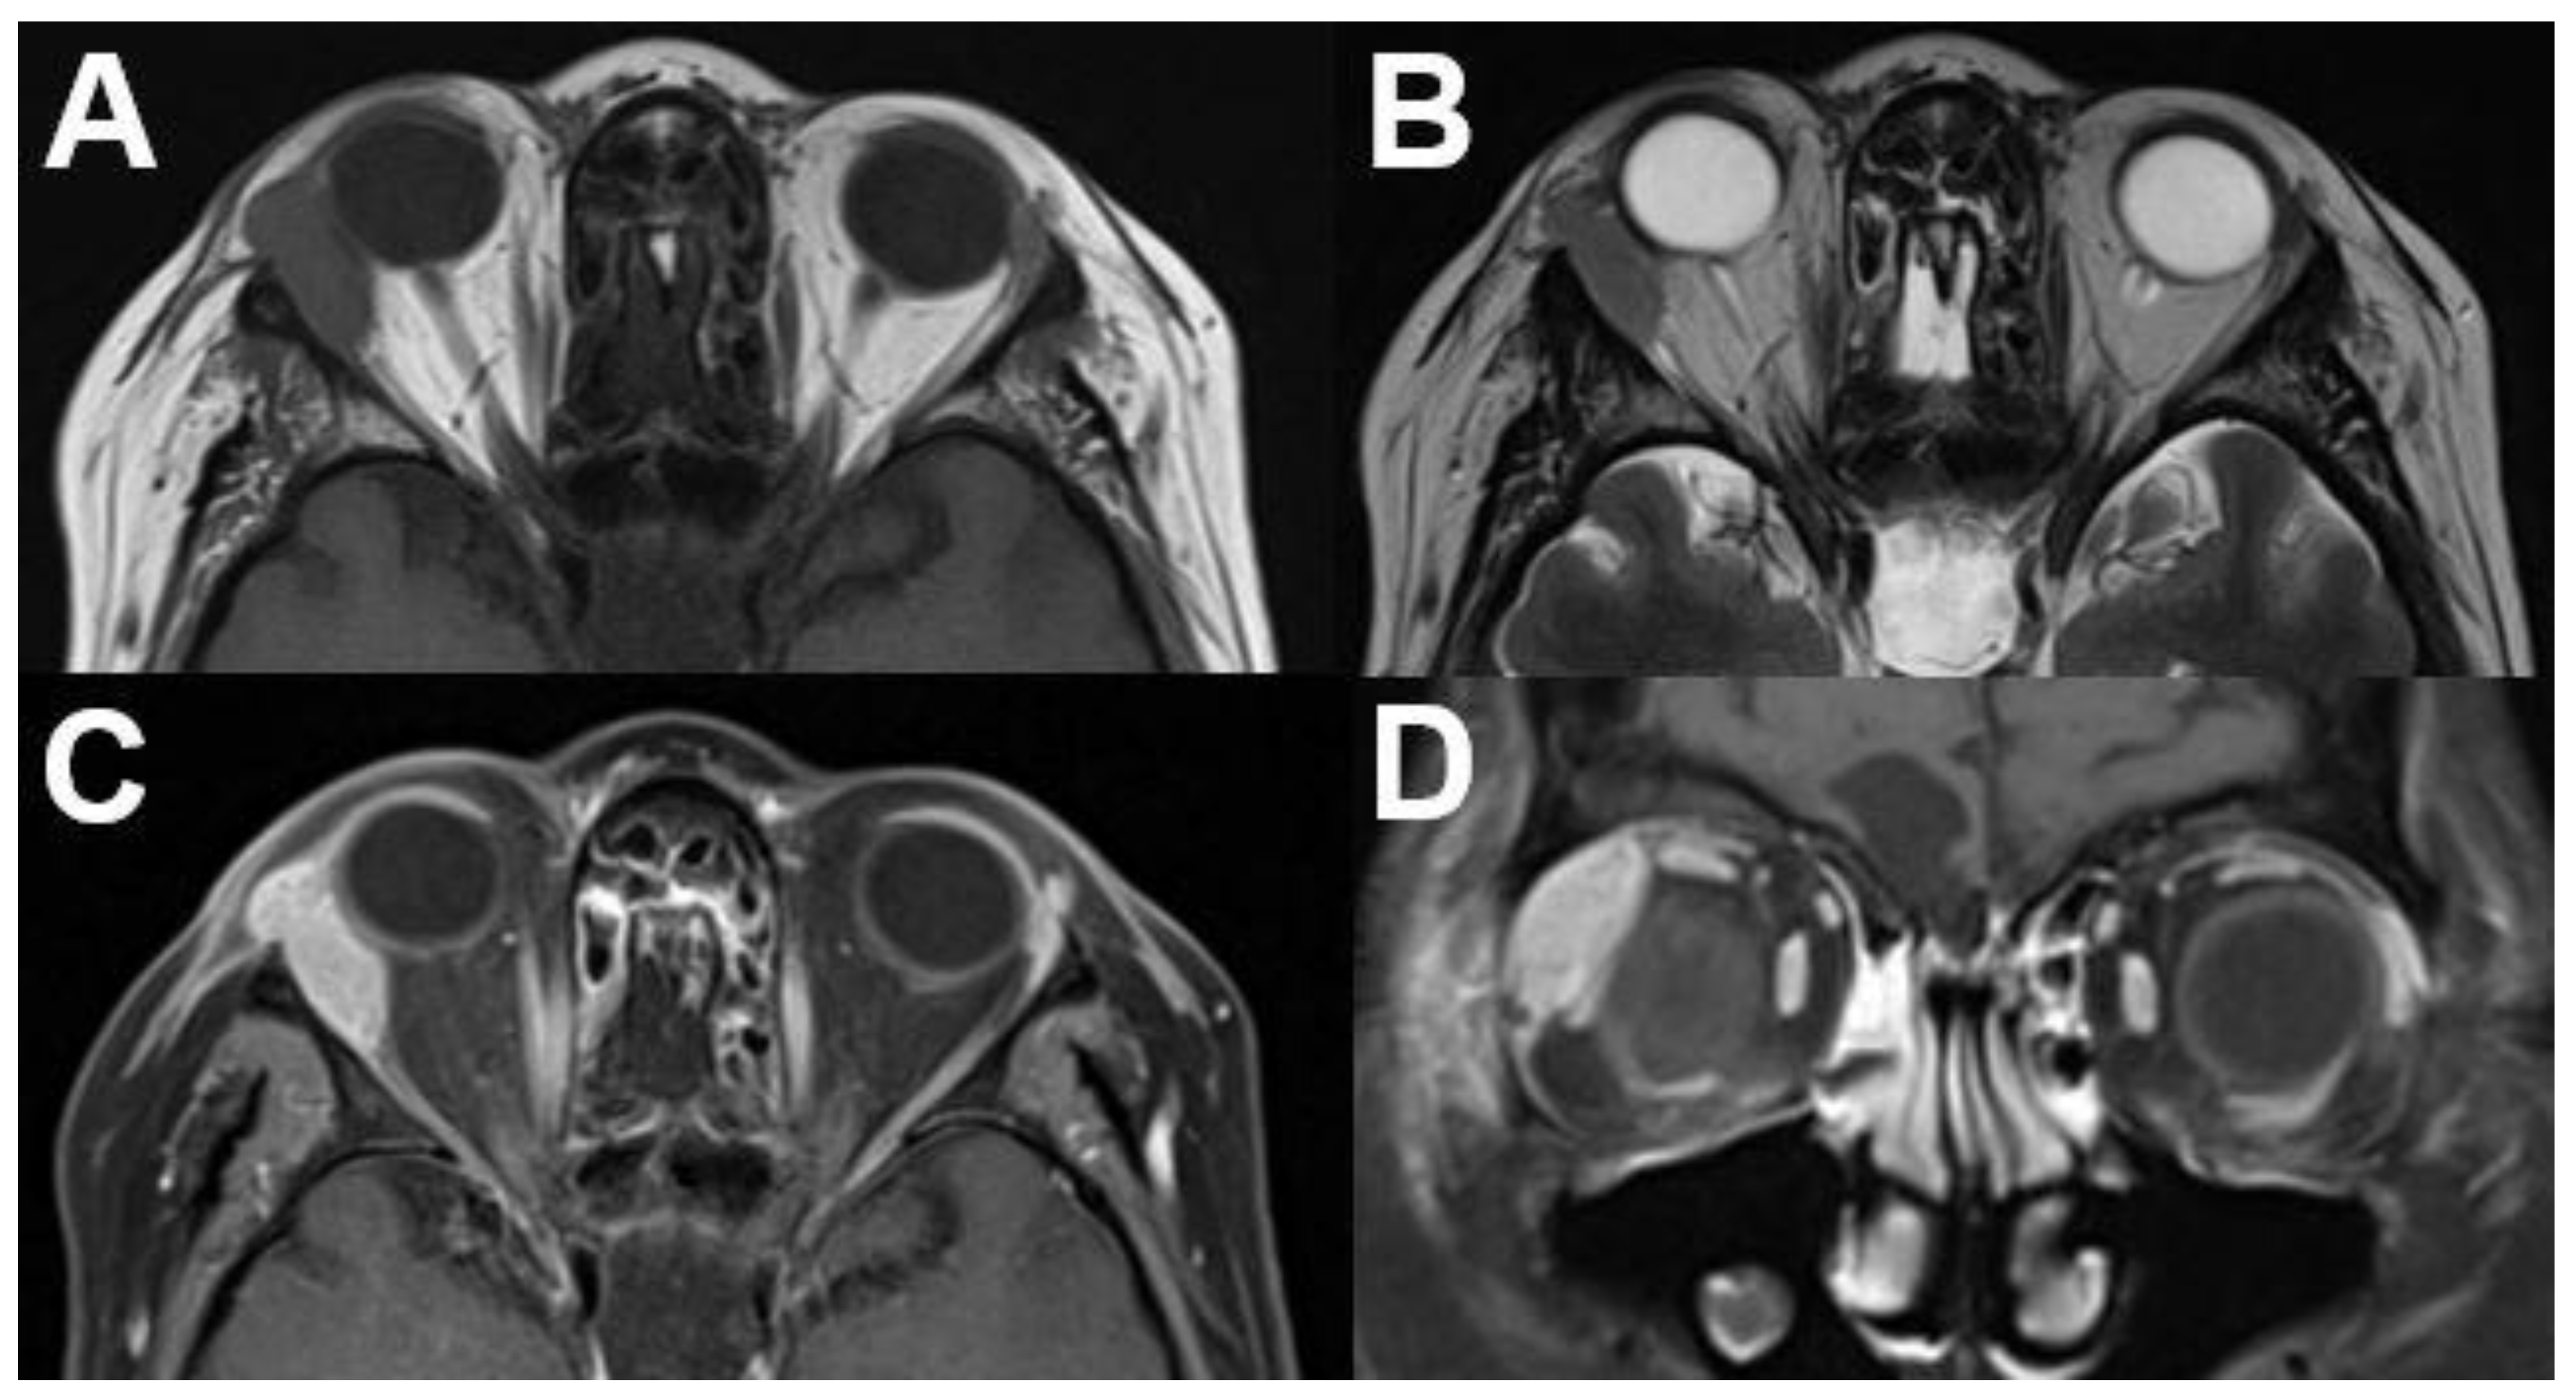

3.1.1. Retinoblastoma